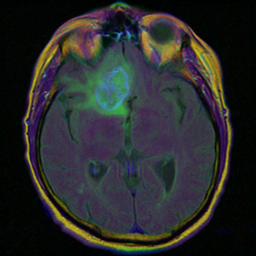

Brain MRI segmentation представляет собой набор из изображений МРТ головного мозга и изображений масок с аномальными участками

Пример данных:

МРТ